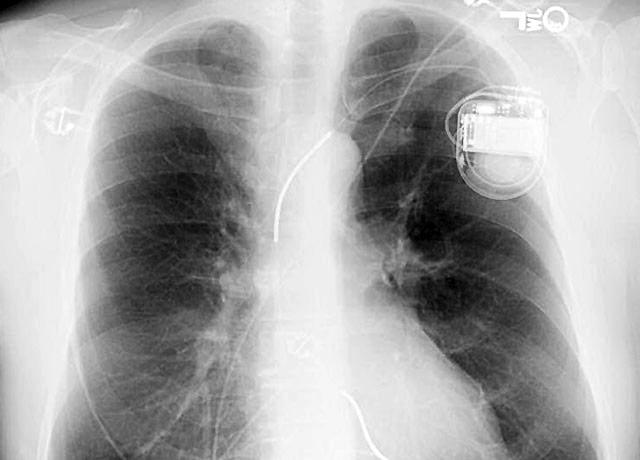

About 30 years ago, doctors started putting implantable cardioverter defibrillators (ICDs) in patients who had survived a sudden cardiac arrest. These palm-size devices, wired to the heart, could stave off another such event by recognizing a dangerous rhythm and providing a lifesaving shock, returning the organ to normalcy.